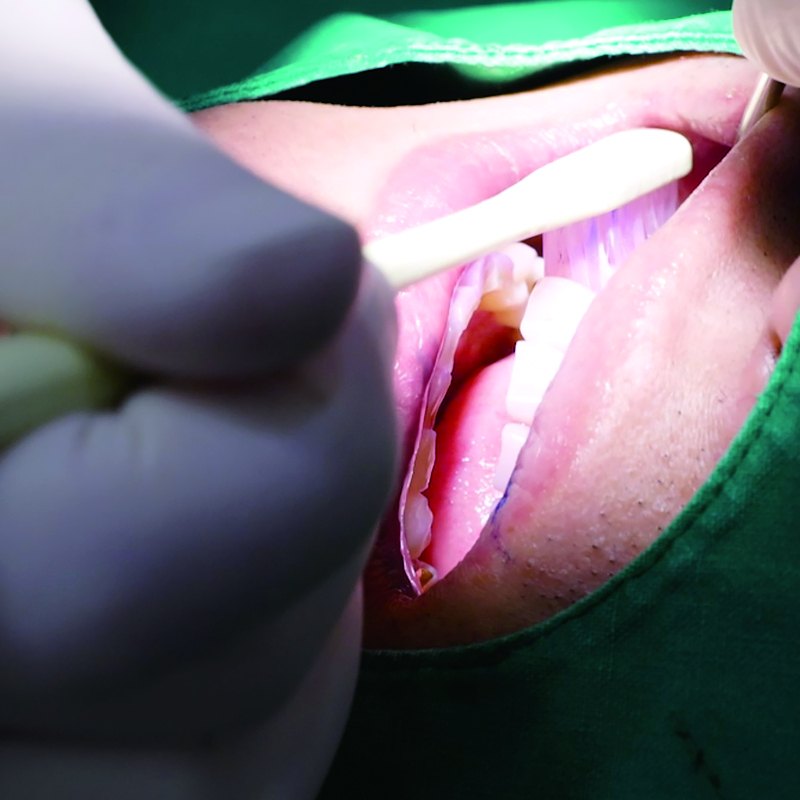

임플란트 깊숙한 틈까지 깨끗하게 관리해드립니다

임플란트는 시술 후 관리가 더 중요합니다

임플란트 식립 이후에 제대로 된 유지 관리가 이뤄지지 않는다면, 여러 문제가 발생할 수 있습니다.

치태나 치석이 쌓여 치주염과 유사한 증상인 잇몸이 붓고 출혈이 발생하는 임플란트 주위염이 발생할 수 있습니다.